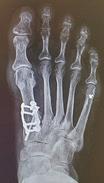

EAST COUNTY OBSERVER | THURSDAY, OCTOBER 6, 2022 5AYourObserver.com 389926-1 BUNIONS? Lapiplasty® by Limon fixes the root of the problem, addresses all 3 dimensions and you can walk within days of surgery! Dr. Lisa Griffith-Limon DPM, D-ACFAS is a Centurion Lapiplasty® Specialist: An honor only awarded to surgeons who have completed over 100 Lapiplasty® procedures!BEFORE AFTER ü Returns entire bone to normal alignment; a 3D correction ü Secures the root cause; an unstable joint ü Get back on your feet quickly in a boot; many cases within 2 weeks MOST INSURANCE ACCEPTED OPEN BY APPOINTMENT 11065 Gatewood Dr, Bldg C2, Lakewood Ranch 4614 26th Street W, Bradenton Serving Manatee County since 1998 Schedule to see if it’s right for you! 941.782.8639 LimonsFoot.com • Hundreds of home sellers like you have saved over $2.6MM with REALean! • Keep more of your home’s equity! • 21 Years experience, integrity, knowledge and detailed care. • Call me today to find out what your home is worth in today’s market! Home Sellers... Karen Nasello, Realtor since 2001 941-219-5959 Karen@Realean.com How would you like to pay ONLY 4% or less* to sell your home, while enjoying CONCIERGE-LEVEL Full Service? *3% if I am the only agent involved in the sale. New Listing Country Club East - Coach Home $758,900 Saving Sellers over $15,000 SOLD Tierra Verde - Lux Waterfront $2,150,000 Saving sellers over $40,000 382416-1 374085-1 HURRICANE SUPPORT NEEDED Cat Depot is in need of hurricane recovery support. Cash donations, cat food, or anything on our wish list would be much appreciated. 941-366-2404 | 2542 17th St., Sarasota, FL 34234 Donate today at www.catdepot.org 379617-1 to life preservers and guided them to higher ground.